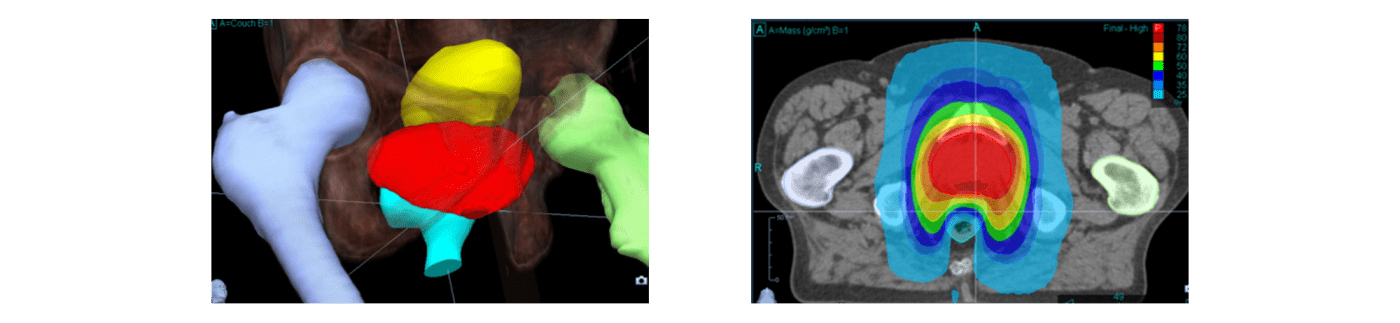

전립선암의 치료 예

정상 조직에 해당하는 선량을 억제한 치료가 가능

직장 등의 장기를 피하여 자유자재로 조사할 수 있음